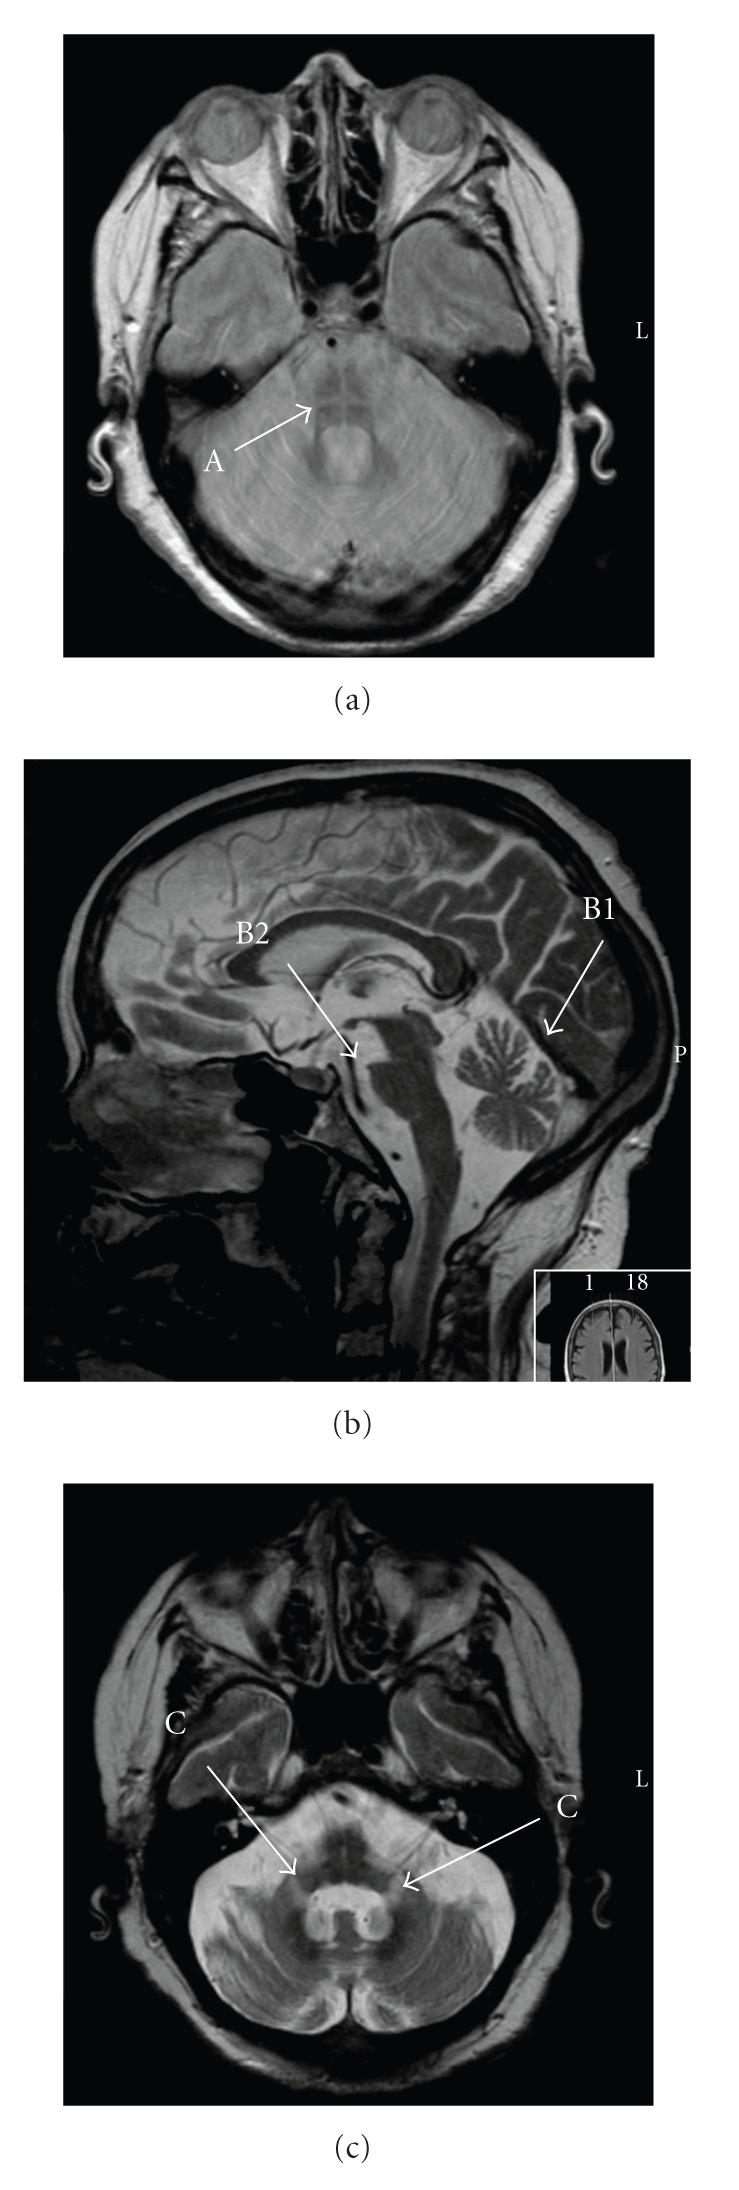

Background. MSA (Multiple System Atrophy) may be associated either with Parkinsonism or with cerebellar ataxia (MSA-c subtype). It is considered a rare disease, but many patients are misdiagnosed as suffering from idiopathic Parkinson's disease. In this paper, we report a case of a patient admitted with respiratory failure and vocal cords paralysis due to MSA-c. Case Report. A 79-year-old Caucasian woman was admitted in March 2010 with dyspnea, asthenia, stridor, and respiratory failure needing noninvasive ventilation. She had orthostatic blood pressure decline, constipation, insomnia, daytime sleepiness, and snoring. The neurologic examination revealed cerebellar ataxia. A laryngoscopy revealed vocal cord paralysis in midline position and tracheostomy was performed. The Brain Magnetic Resonance Imaging revealed atrophy of middle cerebellar peduncles and pons with the "hot cross bun sign." Conclusion. Although Multiple-system atrophy is a rare disease, unexplained respiratory failure, bilateral vocal cord paralysis, or stridor should lead to consider MSA as diagnosis.

背景。多系统萎缩(MSA)可能与帕金森综合征或小脑共济失调(MSA-c亚型)相关。它被认为是一种罕见疾病,但许多患者被误诊为特发性帕金森病。在本文中,我们报告了一例因MSA-c导致呼吸衰竭和声带麻痹而入院的患者。病例报告。一名79岁的白种女性于2010年3月因呼吸困难、乏力、喘鸣和呼吸衰竭需要无创通气而入院。她有体位性血压下降、便秘、失眠、日间嗜睡和打鼾症状。神经系统检查发现小脑共济失调。喉镜检查显示声带麻痹处于中线位置,并进行了气管切开术。脑部磁共振成像显示小脑中间脚和脑桥萎缩伴有“热十字面包征”。结论。尽管多系统萎缩是一种罕见疾病,但不明原因的呼吸衰竭、双侧声带麻痹或喘鸣应考虑将MSA作为诊断。